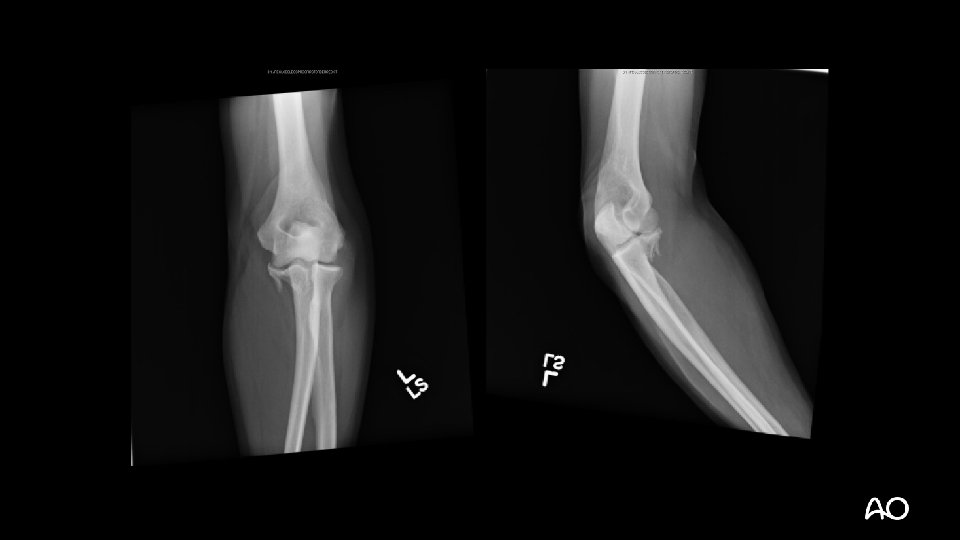

Case 1

Terrible triad fracture dislocation • Historically poor outcomes • Injury “triad”: • Elbow dislocation (often posterior) • Radial head fracture • Coronoid fracture